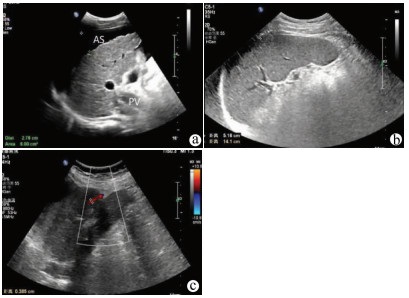

Guideline for ultrasonic diagnosis of liver diseases

Chinese Society of Ultrasound in Medicine, Oncology Intervention Committee of Chinese Research Hospital Society, National Health Commission Capacity Building and Continuing Education Expert Committee on Ultrasonic Diagnosis

2021, 37(8): 1770-1785. DOI: 10.3969/j.issn.1001-5256.2021.08.007

Abstract(3025) HTML (6526) PDF (9311KB)(794)

Abstract:

Ultrasound is a non-invasive, real-time, inexpensive, radiation-free and easily repeatable method, usually used for liver imaging. In recent years, new ultrasound examination techniques for liver diseases such as contrast-enhanced ultrasound and elastography have been rapidly developed, which can effectively identify intrahepatic space-occupying lesions, assess the degree of liver fibrosis and portal hypertension, and monitor the effects of treatment. Therefore, these technologies play an important diagnostic role in clinical liver diseases and have therapeutic interventional value. This guideline classifies the instrument set-up, patient preparation, and physician examination methods through multimodal ultrasound examinations (gray-scale ultrasound, color Doppler ultrasound, contrast-enhanced ultrasound, elastic ultrasound) for liver diseases. In addition, liver diseases multimodal ultrasound technology diagnostic criteria for diffuse hepatic lesions (inflammatory lesions, fibrosis, and sclerosis), multiple space-occupying lesions, and interventional procedures have been defined and standardized. Concurrently, we also recommend the ultrasound monitoring time interval and diagnostic report writing standard for liver diseases.